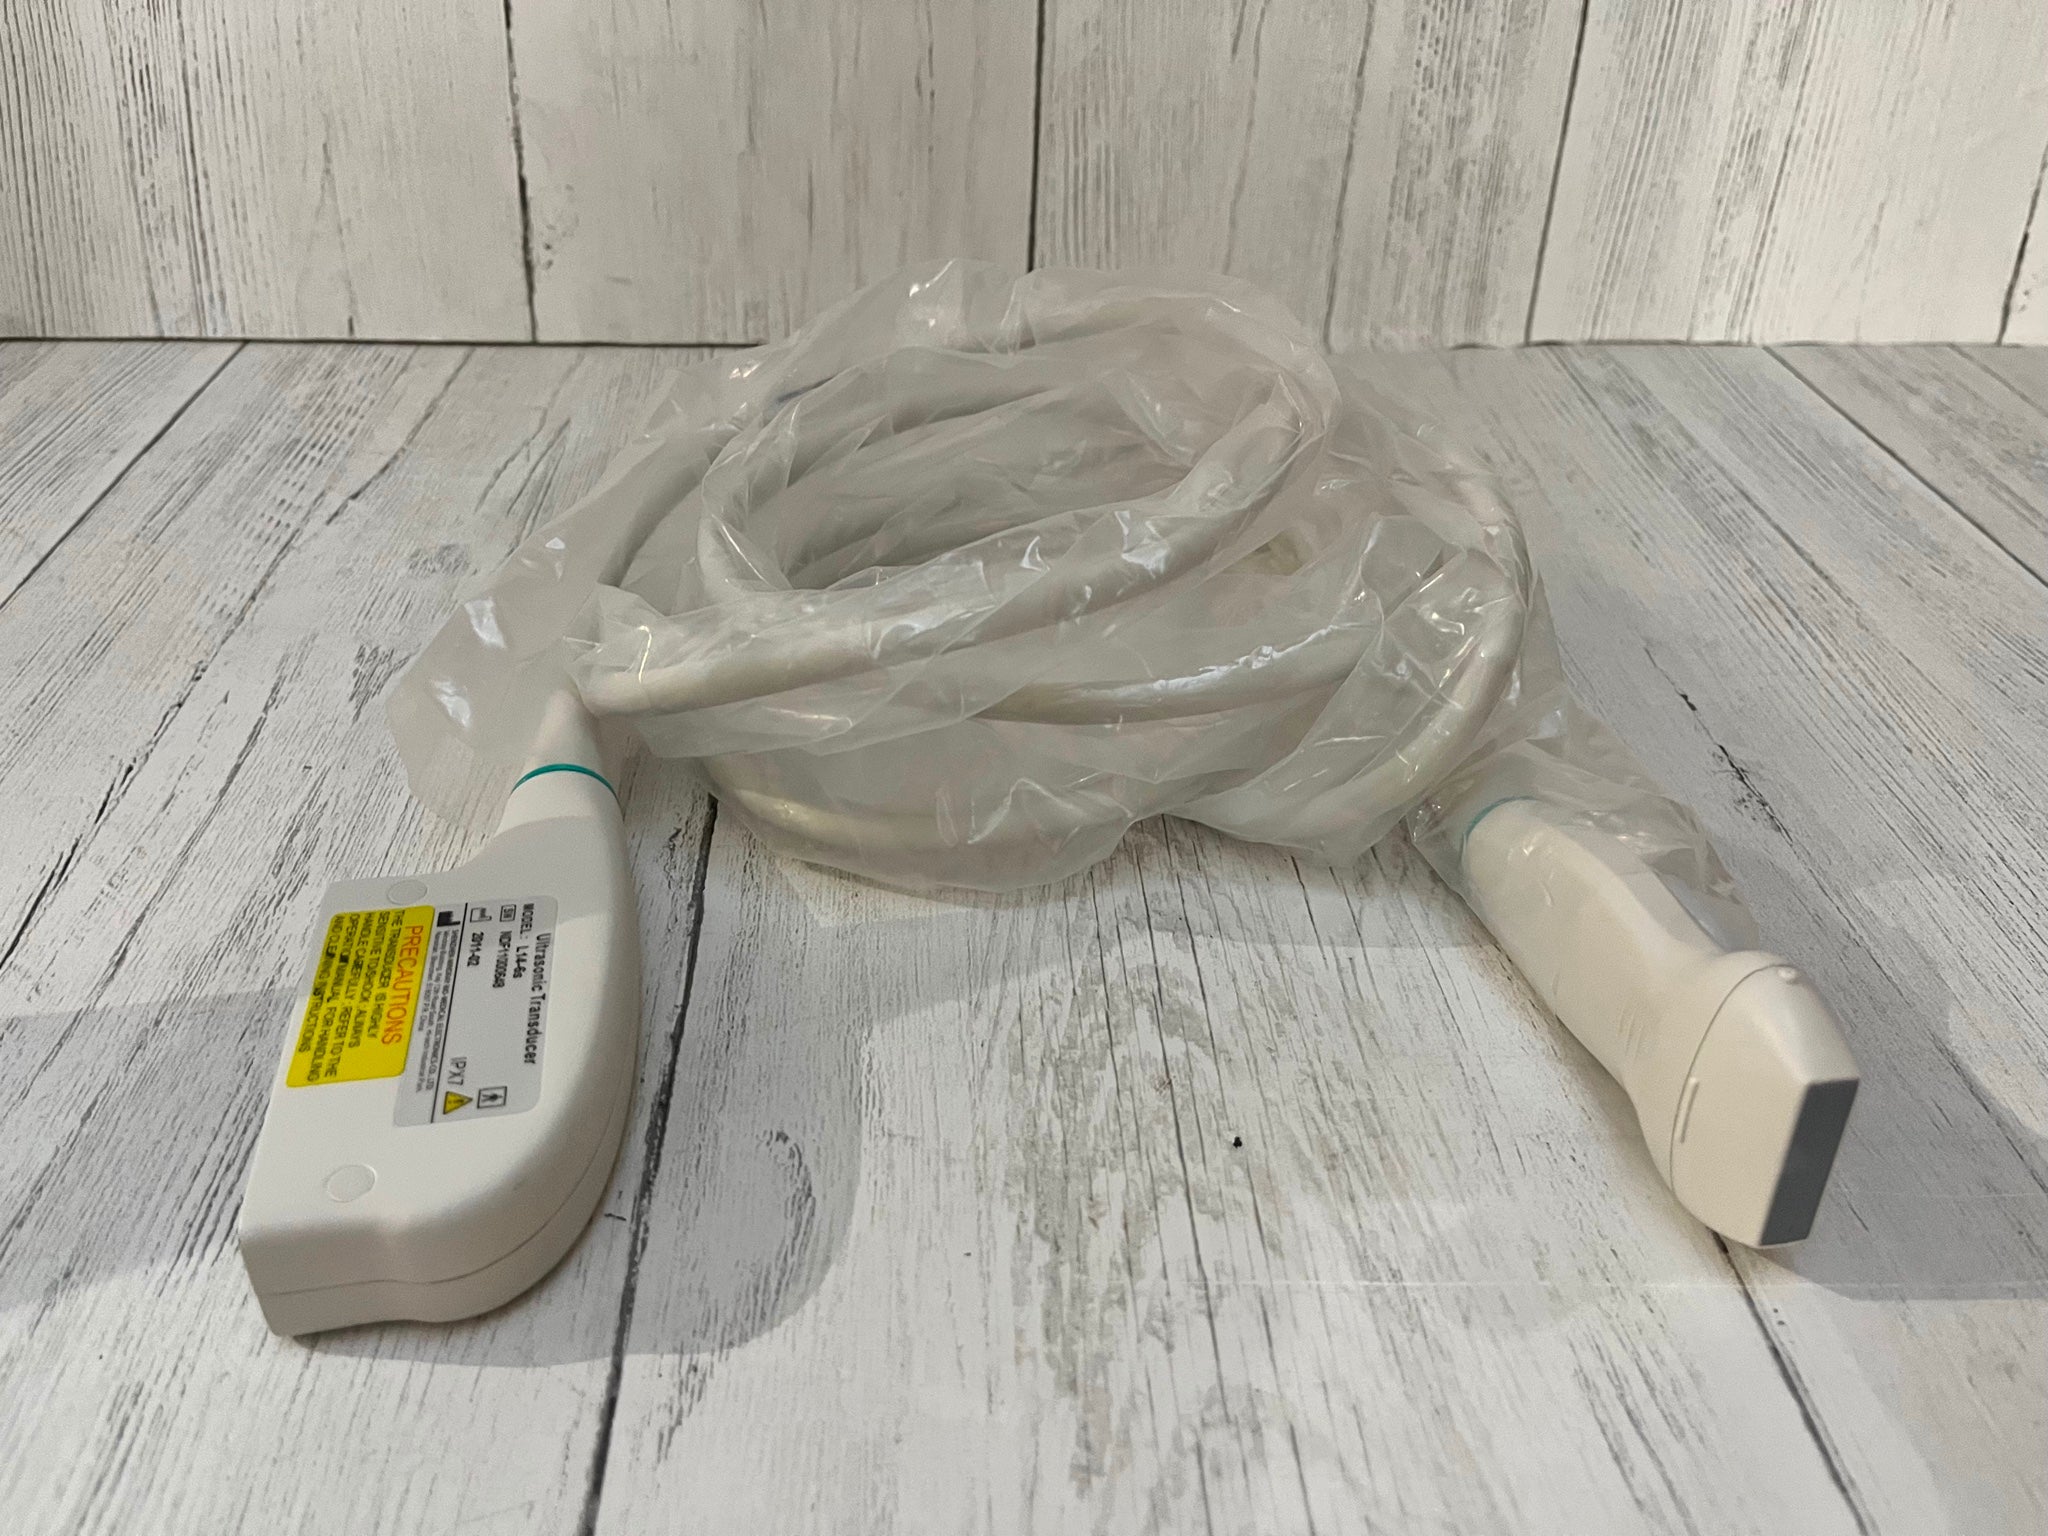

Ease of Use and Portability

One of the defining features of the Laptop Ultrasound Scanner is its user-friendly interface and lightweight design. This portable device makes conducting ultrasounds simpler than ever before. Clinicians can quickly set it up and start scanning without extensive training. The compact nature also allows for easy transportation between different patient locations. Therefore, whether you are in a hospital or a clinic, you can have this ultrasound scanner at your fingertips.